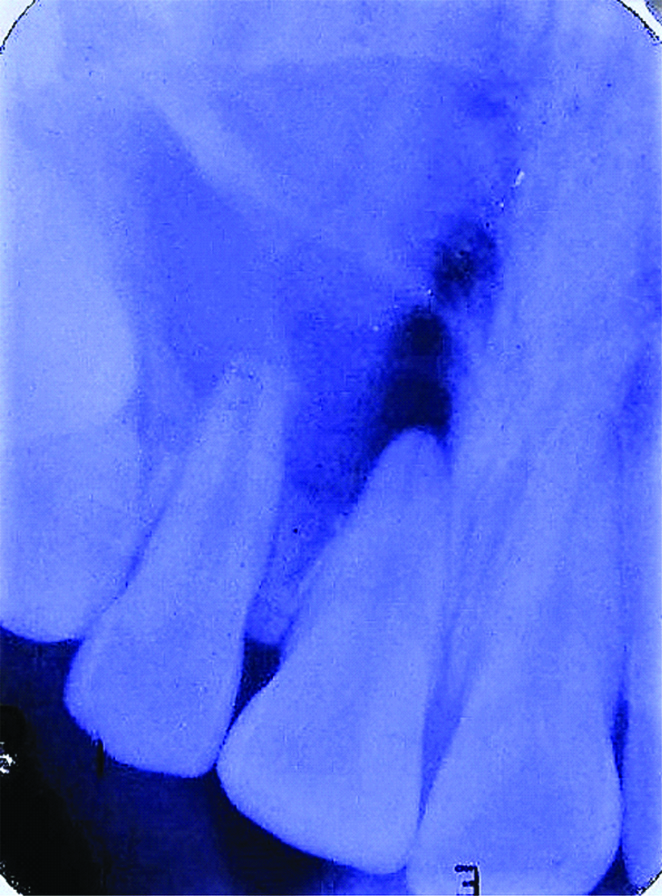

A 19-year-old female patient presented with a non-tender swelling in the right anterior maxillary region of one month duration. A history of trauma 10 years ago was reported in the same site which was uneventful. On intraoral examination the swelling was diffuse, well defined in relation to 11 and 12 region. On palpation the swelling was soft to firm in consistency, adherent to the overlying mucosa. Electric pulp testing of 11 and 12 showed no response. This indicated non-vital teeth. The lesion was provisionally diagnosed as Periapical cyst. Differential diagnosis of Periapical granuloma was given. Radiographic examination revealed an ovoid radiolucency in relation to the periapical region of 11 and 12. The lesion was well defined and extending from mesial of 11 to mesial of 13, measuring 1×1 cm [Table/Fig-1].

Periapical radiograph showing radiolucency in relation to the apical region of 11 and 12.